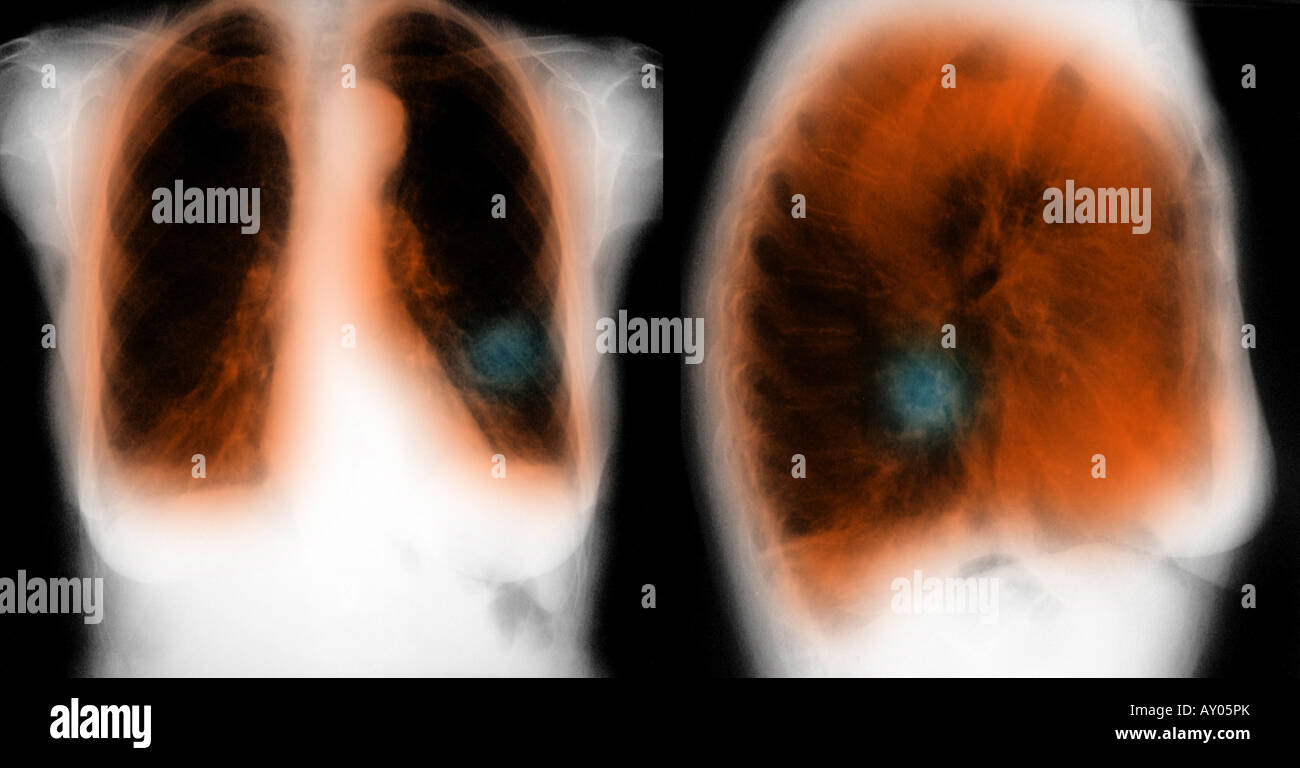

chest xray showing COPD (chronic obstructive pulmonary disease) and Image Of Chest X Ray With Copd This image shows no abnormality at the left lung base. Copd lungs often appear hyperinflated compared to healthy lungs. It uses electromagnetic radiation to create pictures of the lungs,. Comparison of the two images makes it. Tap on/off image to show/hide findings. This means that the lung tissue is expanded and the lungs appear larger than. Image Of Chest X Ray With Copd.

Xray of chest showing COPD Stock Photo Alamy Image Of Chest X Ray With Copd It uses electromagnetic radiation to create pictures of the lungs,. Copd lungs often appear hyperinflated compared to healthy lungs. This means that the lung tissue is expanded and the lungs appear larger than. Comparison of the two images makes it. Tap on/off image to show/hide findings. This image shows no abnormality at the left lung base. Image Of Chest X Ray With Copd.

COPD Xray What it looks like and diagnosis Image Of Chest X Ray With Copd Comparison of the two images makes it. It uses electromagnetic radiation to create pictures of the lungs,. Tap on/off image to show/hide findings. This image shows no abnormality at the left lung base. This means that the lung tissue is expanded and the lungs appear larger than. Copd lungs often appear hyperinflated compared to healthy lungs. Image Of Chest X Ray With Copd.